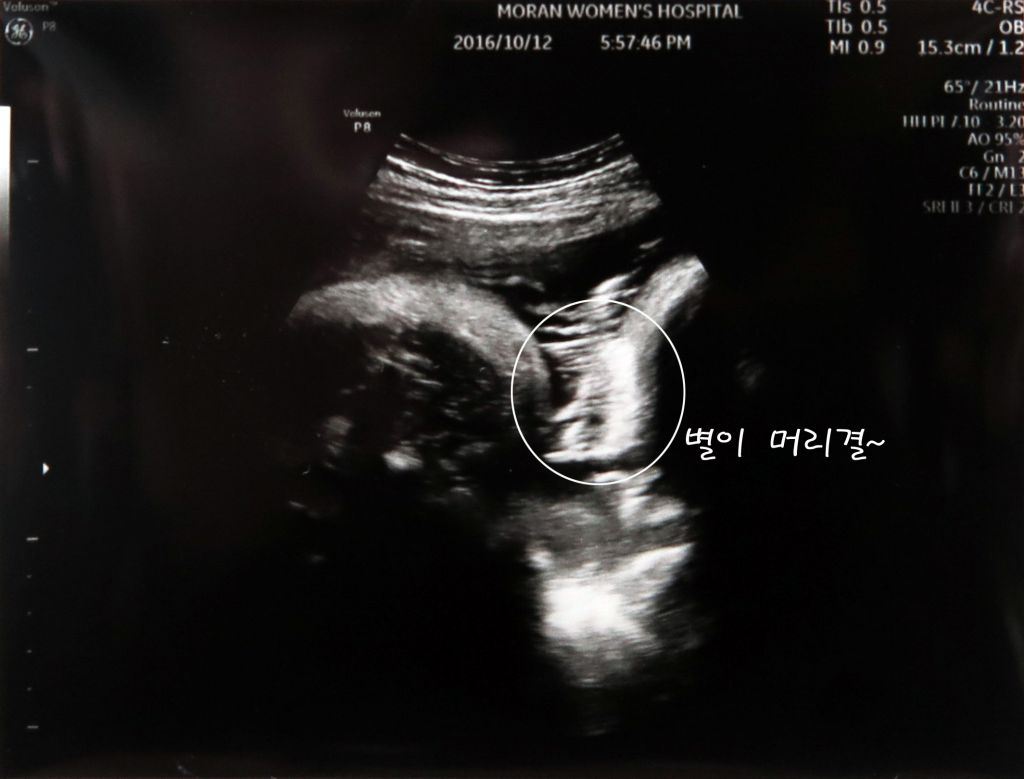

그리고 마지막 사진은 별이 머리카락입니다.ㅎㅎ

별이 어멈이 임신중에 고기를 많이 먹어서 그런지 아빠를 닮아서 그런지 머리숱이 꽤 많아 보이네요^^